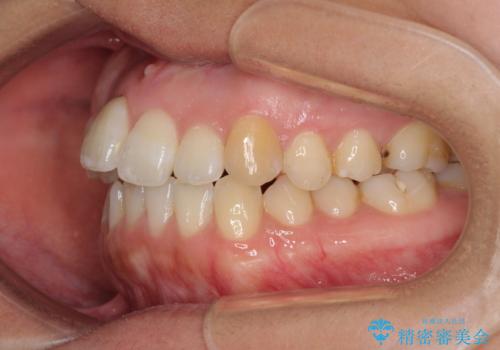

- 上下のデコボコを改善したいとのことで来院された患者様です。

近々妊娠する予定であり、極力短期間で治療したいとのことで、ワイヤー装置による非抜歯矯正治療を行うこととしました。

治療開始後すぐに妊娠され、つわりと闘いながらの矯正治療となりました。

上下顎でゴムかけを行ったのですが、早く終わらすためにしっかりと装着していただき、無事出産前に装置を外すことができました。